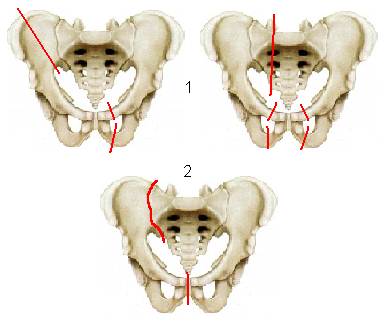

II. Перелом костей тазового кольца без нарушения его непрерывности (рис.2) –

1. Односторонний или двусторонние переломы ветви лонной кости,

2. Односторонний или двусторонние переломы ветви седалищной кости,

3. Перелом лонной с одной стороны и седалищной кости с другой стороны.

III. Переломы костей тазового кольца с нарушением его непрерывности и разрывы сочленений.

А. переднего полукольца (рис3) –

- перелом лонной и седалищной костей с одной стороны

- двусторонние переломы лонной и седалищной костей (типа «бабочки»),

- разрыв симфиза.

Б. заднего отдела (рис.4)–

1. вертикальный перелом подвздошной кости,

2. разрыв крестцово-подвздошного сочленения,

3. вертикальный перелом крестца.

Рис.2. Перелом костей тазового кольца без нарушения его непрерывности.

Рис.3. Переломы костей переднего полукольца с нарушением его непрерывности.

Рис.4. Переломы костей заднего полукольца с нарушением его непрерывности.